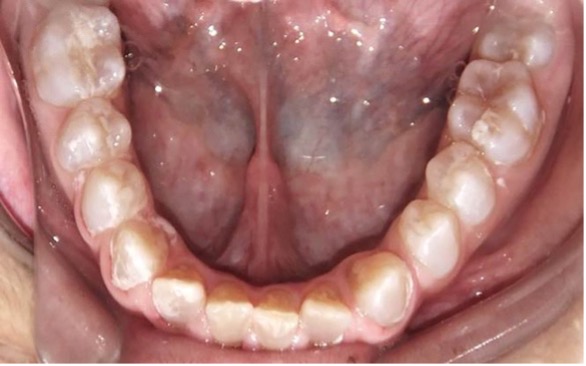

El examen clínico intraoral reveló alteración de la estructura y color de las piezas primarias, atrición y pérdida de la dimensión vertical (Figura 2). Radiográficamente se observó la presencia de coronas con marcada constricción cervical y raíces cortas (Figura 3). Presentaba alto riesgo cariogénico, por la presencia de lesiones de caries activas y dos restos radiculares, sumado a la anomalía estructural de la dentina (riesgo biológico específico) y bajo riesgo gingivoperiodontal. El riesgo socio-económico era alto por provenir de una familia con marcadas limitaciones económicas. Luego de la anamnesis, examen clínico y radiográfico, e interconsulta con el médico de cabecera se estableció el diagnóstico de DI Tipo I asociado a OI tipo I. Se planificó un tratamiento integral y preventivo con los objetivos de devolver forma y función, y proteger y evitar el desgaste de los tejidos conductas que pudieran interferir con el tratamiento.

Figura 2: Examen clínico intraoral del maxilar superior e inferior y vista anterior. Año 2007

En el último control realizado en el año 2018 (Figura 11) el paciente mantuvo el estado de salud logrado. El análisis cariogénico fue moderado (por su historia pasada de caries y su condición biológica específica) y el gingivoperiodontal bajo. El paciente continúa en atención en la COIN. Fue derivado en varias oportunidades al servicio de Ortodoncia de la Facultad de Odontología de la Universidad de Buenos Aires, pero hasta el momento no encaró ningún tratamiento propuesto.

Figura 11: Controles clínicos 2018

Cuando la dentición permanente está implicada, los incisivos inferiores son los más comprometidos, presentando en estos casos una coloración intensa propia de la DI (O’Connell, Marini 1999, Majorana, Bardellini et al. 2010, Petersen, Wetzel 1998), como se observa en el paciente. Las piezas permanentes fueron monitoreadas desde su erupción, recibieron protocolos preventivos con barnices fluorados, pastas y enjuagatorios fluorados domiciliarios, conjuntamente con un adecuado control de higiene oral.15